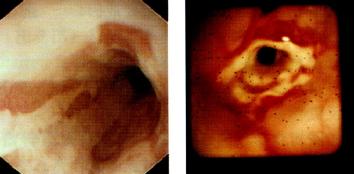

内镜(图3.15)

为诊断食管炎的金标准,既可对食管炎进行观察和分型,又可行食管粘膜活检。

以下为Savary和Miller制定的食管炎内镜下分型:

. Ⅰ期:单个或多个纵行非融合的红斑性粘膜损害,常覆有渗出物,发生于胃食和连接处上方或由连接处延伸开来

. Ⅱ期:融合性糜烂和渗出性粘膜损害,但并未累及食管全周

. Ⅲ期:全周性糜烂及渗出病变,覆盖整个食管粘膜

. Ⅳ期:慢性粘膜损害,如伴或不伴狭窄的溃疡

食管远端内镜所见

图3.15食管远端内镜所见。(a)线状充血糜烂:反流性食管炎。图取自

Cotton & Williams,Practical Gastrointestinal Endoscopy,3rd edn,

1990(Blackwell Science,Oxford),经作者许可。(b)消化性食管狭窄